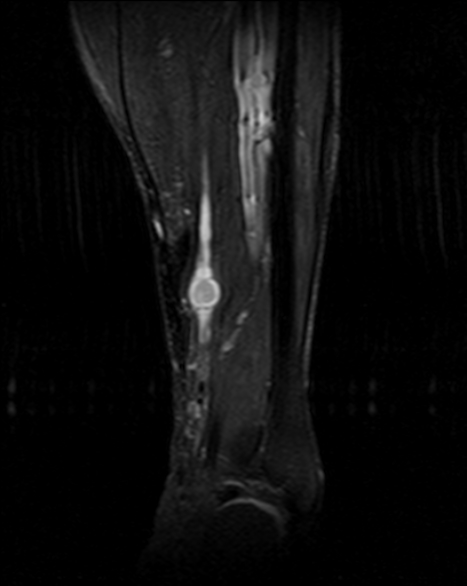

4.2 RM con contraste (prueba de elección)

- T1: señal baja–intermedia respecto a músculo.

- T2/STIR: señal alta, a menudo heterogénea (degeneración quística en schwannomas antiguos).

- Signos orientativos: relación con el nervio (fascículo entrante/saliente), “fascicular sign”, “split-fat sign” (en planos profundos). El “target sign” no es exclusivo.

- Contraste: realce de componente sólido; las áreas quísticas no realzan.